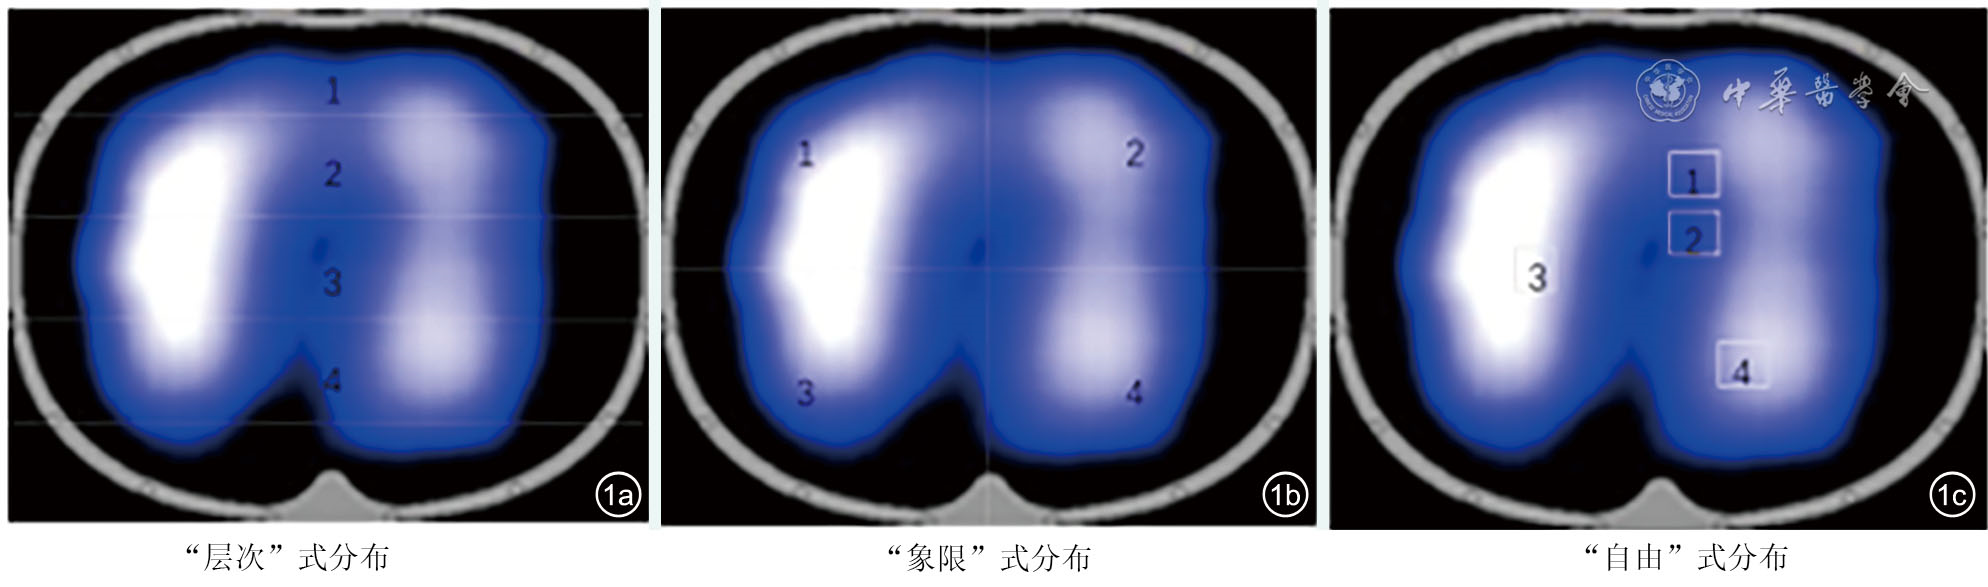

Postoperative pulmonary complications (PPC) are one of the most challenging complications faced by patients after cardiac surgery, and are the major cause of postoperative mortality. Electrical impedance tomography (EIT) is a kind of noninvasive bedside lung ventilation monitoring technology which is used increasingly in intensive respiratory management. Recently, it has been found that EIT lung ventilation imaging features can be used to predict the occurrence of PPC after abdominal surgery. Based on the practical experience of EIT application in our center, this paper summarizes the PPC diagnosis and treatment strategy based on EIT lung ventilation image feature, in order to provide reference for the application of EIT technology in cardiac surgery.